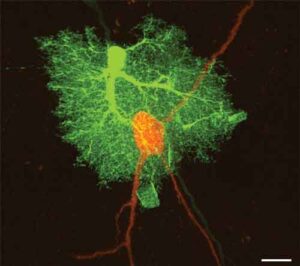

Nuove ricerche pubblicate sul 'Journal of Neuroscience' suggeriscono che modificando i segnali inviati dagli astrociti, cellule cerebrali a forma di...